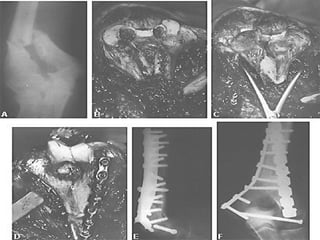

CLASIFICACION Las clasificaciones complementarias se basan en el grado de lesión de partes blandas, siendo la mas utilizada la de Gustilo

CLASIFICACION DE GUSTILLO I:  Herida < 1 cm. Herida limpia realizada por un fragmento puntiagudo de hueso que perfora la piel, existe escasa lesión a tejidos blandos, sin signos de aplastamiento, son por baja energía

CLASIFICACION DE GUSTILLO II:  Longitud > 1 cm. Sin colgajos, avulsiones y sin una gran lesión de tejido blando, existe un mínimo a moderado aplastamiento, conminución y contaminación moderada

CLASIFICACION DE GUSTILLO III:  Lesión extensa de tejidos blandos que afectan al músculo, piel y estructuras neurovasculares, suele existir un alto grado de contaminación, son por alta energía A)  cobertura adecuada de tejido blando del hueso, sin importar el tamaño de la herida

CLASIFICACION DE GUSTILLO B)  Afectación extensa o perdida del tejido blando con exposición del hueso, contaminación masiva y una grave fractura conminuta C)  Se asocia a lesión arterial  que necesita reparación independientemente del grado de lesión del tejido blando

CLASIFICACION Las clasificacionescomplementarias se basan en el grado de lesión de partes blandas, siendo la mas utilizada la de Gustilo

CLASIFICACION DE GUSTILLOI: Herida < 1 cm. Herida limpia realizada por un fragmento puntiagudo de hueso que perfora la piel, existe escasa lesión a tejidos blandos, sin signos de aplastamiento, son por baja energía

CLASIFICACION DE GUSTILLOII: Longitud > 1 cm. Sin colgajos, avulsiones y sin una gran lesión de tejido blando, existe un mínimo a moderado aplastamiento, conminución y contaminación moderada

CLASIFICACION DE GUSTILLOIII: Lesión extensa de tejidos blandos que afectan al músculo, piel y estructuras neurovasculares, suele existir un alto grado de contaminación, son por alta energía A) cobertura adecuada de tejido blando del hueso, sin importar el tamaño de la herida

CLASIFICACION DE GUSTILLOB) Afectación extensa o perdida del tejido blando con exposición del hueso, contaminación masiva y una grave fractura conminuta C) Se asocia a lesión arterial que necesita reparación independientemente del grado de lesión del tejido blando